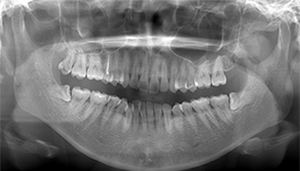

- 抜歯前写真(レントゲン)

- 抜歯前写真(CT画像)

| 抜歯内容 | 左下親知らずが横向きになって半分埋まっている状態だったため、麻酔を行い、親知らずの奥の歯ぐきに切開をいれ、歯が囲んでいる骨を削り、歯の頭の部分を削って出し、その後根の部分に器具をかけて抜歯しました。 親知らずが一部神経に近い部分があったため、術後に麻痺が出る可能性がありました。このケースでは事前にCTを撮影し、歯の位置、根の方向、神経との距離を確認していたため、幸い麻痺が出ることはありませんでした。 術後1週間経過して糸取りをして治療は終了となりました。抜歯後3日間は腫れと痛みで大変だったが、糸取りをする頃には痛みも腫れも無くなったと患者さまも喜んでおられました。 |